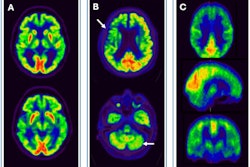

FDG, early perfusion amyloid-PET, and late standard amyloid-PET in a patient with Alzheimer’s disease (AD) ([F-18] Flutemetamol, panel A) and in a patient with behavioral variant of fronto-temporal dementia (bvFTD) ([F-18] Florbetaben, panel B). Regardless of the disease-related pattern (posterior in patient A and anterior in patient B), FDG and early perfusion imaging show largely overlapping distribution with small differences. Higher early-phase amyloid tracer distribution with respect to FDG uptake is expected in the brain stem, cerebellum, anterior cingulate, and thalamus, while lower uptake compared to FDG is present in the prefrontal, orbitofrontal, posterior parietal, and superior temporal regions.Prof. Silvia Morbelli et al and EANM Journal